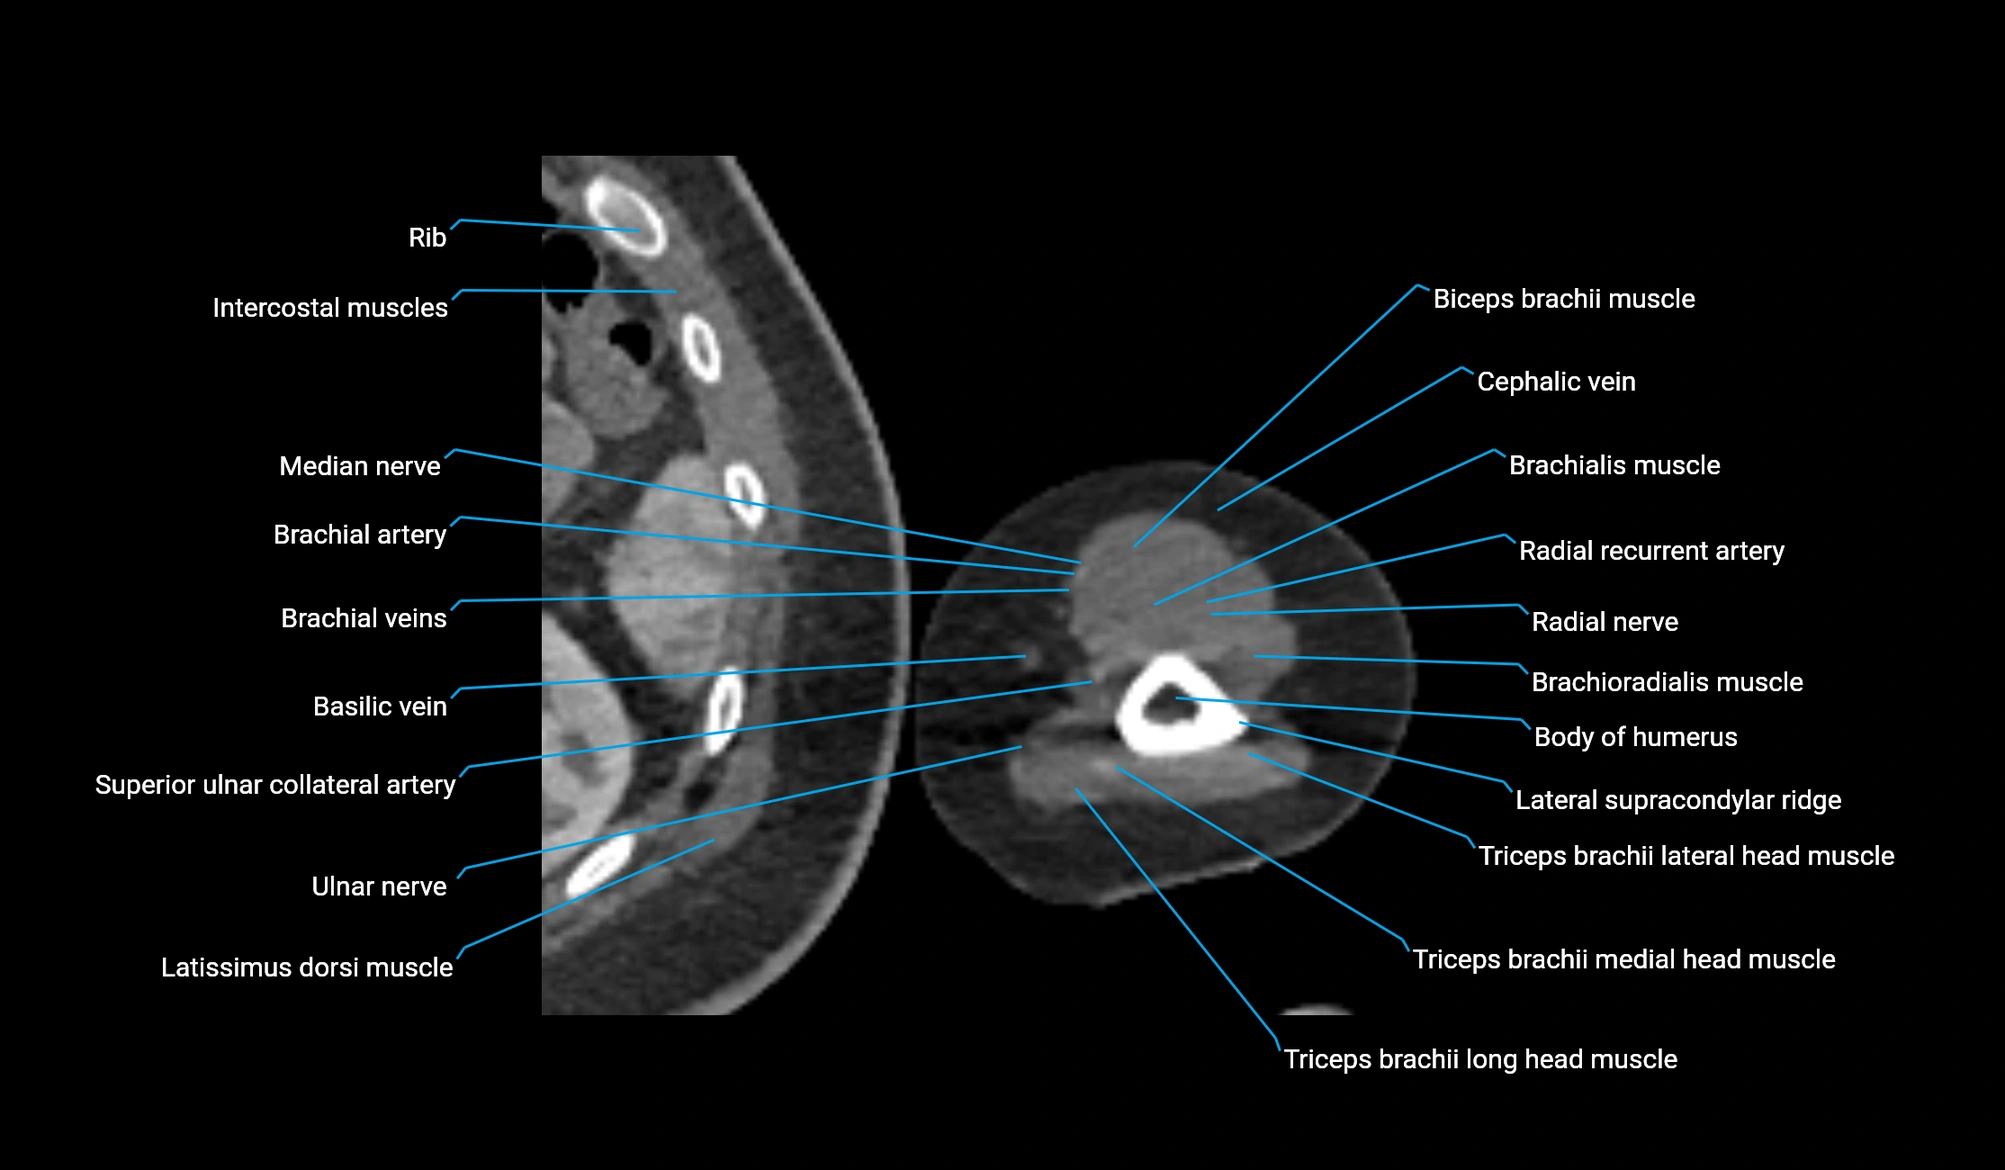

CT image